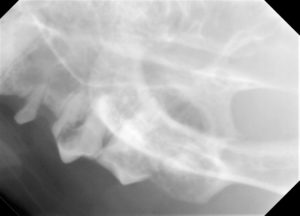

2.レントゲンでは歯の吸収病巣も認められます。